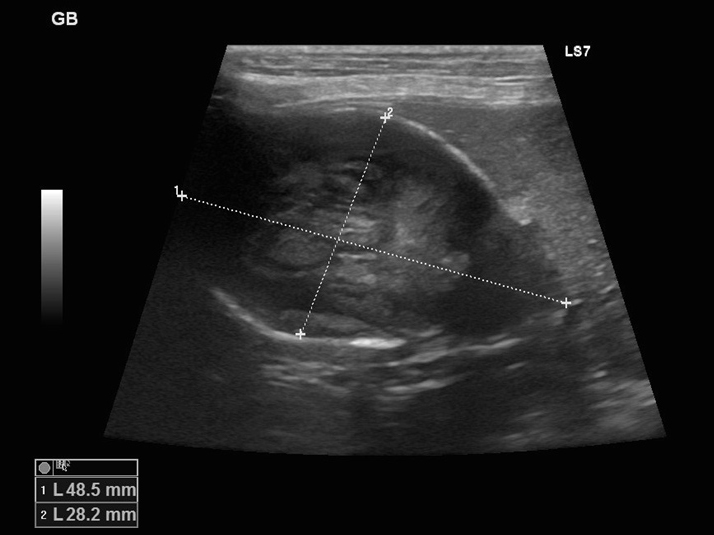

エコー検査では胆嚢の中を満たすほど胆泥が溜まっています。

エコーで胆嚢炎と胆嚢粘液嚢腫であることを確認し、破裂の危険性を考えて腹腔鏡下胆嚢摘出術を実施することになりました。